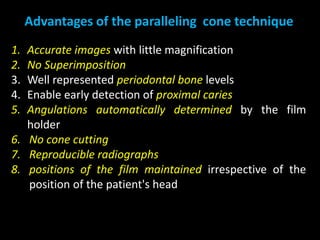

2. The paralleling cone technique provides accurate images with little magnification and no superimposition but is more difficult for patients. The bisecting angle technique is easier for patients but results in more image distortion.